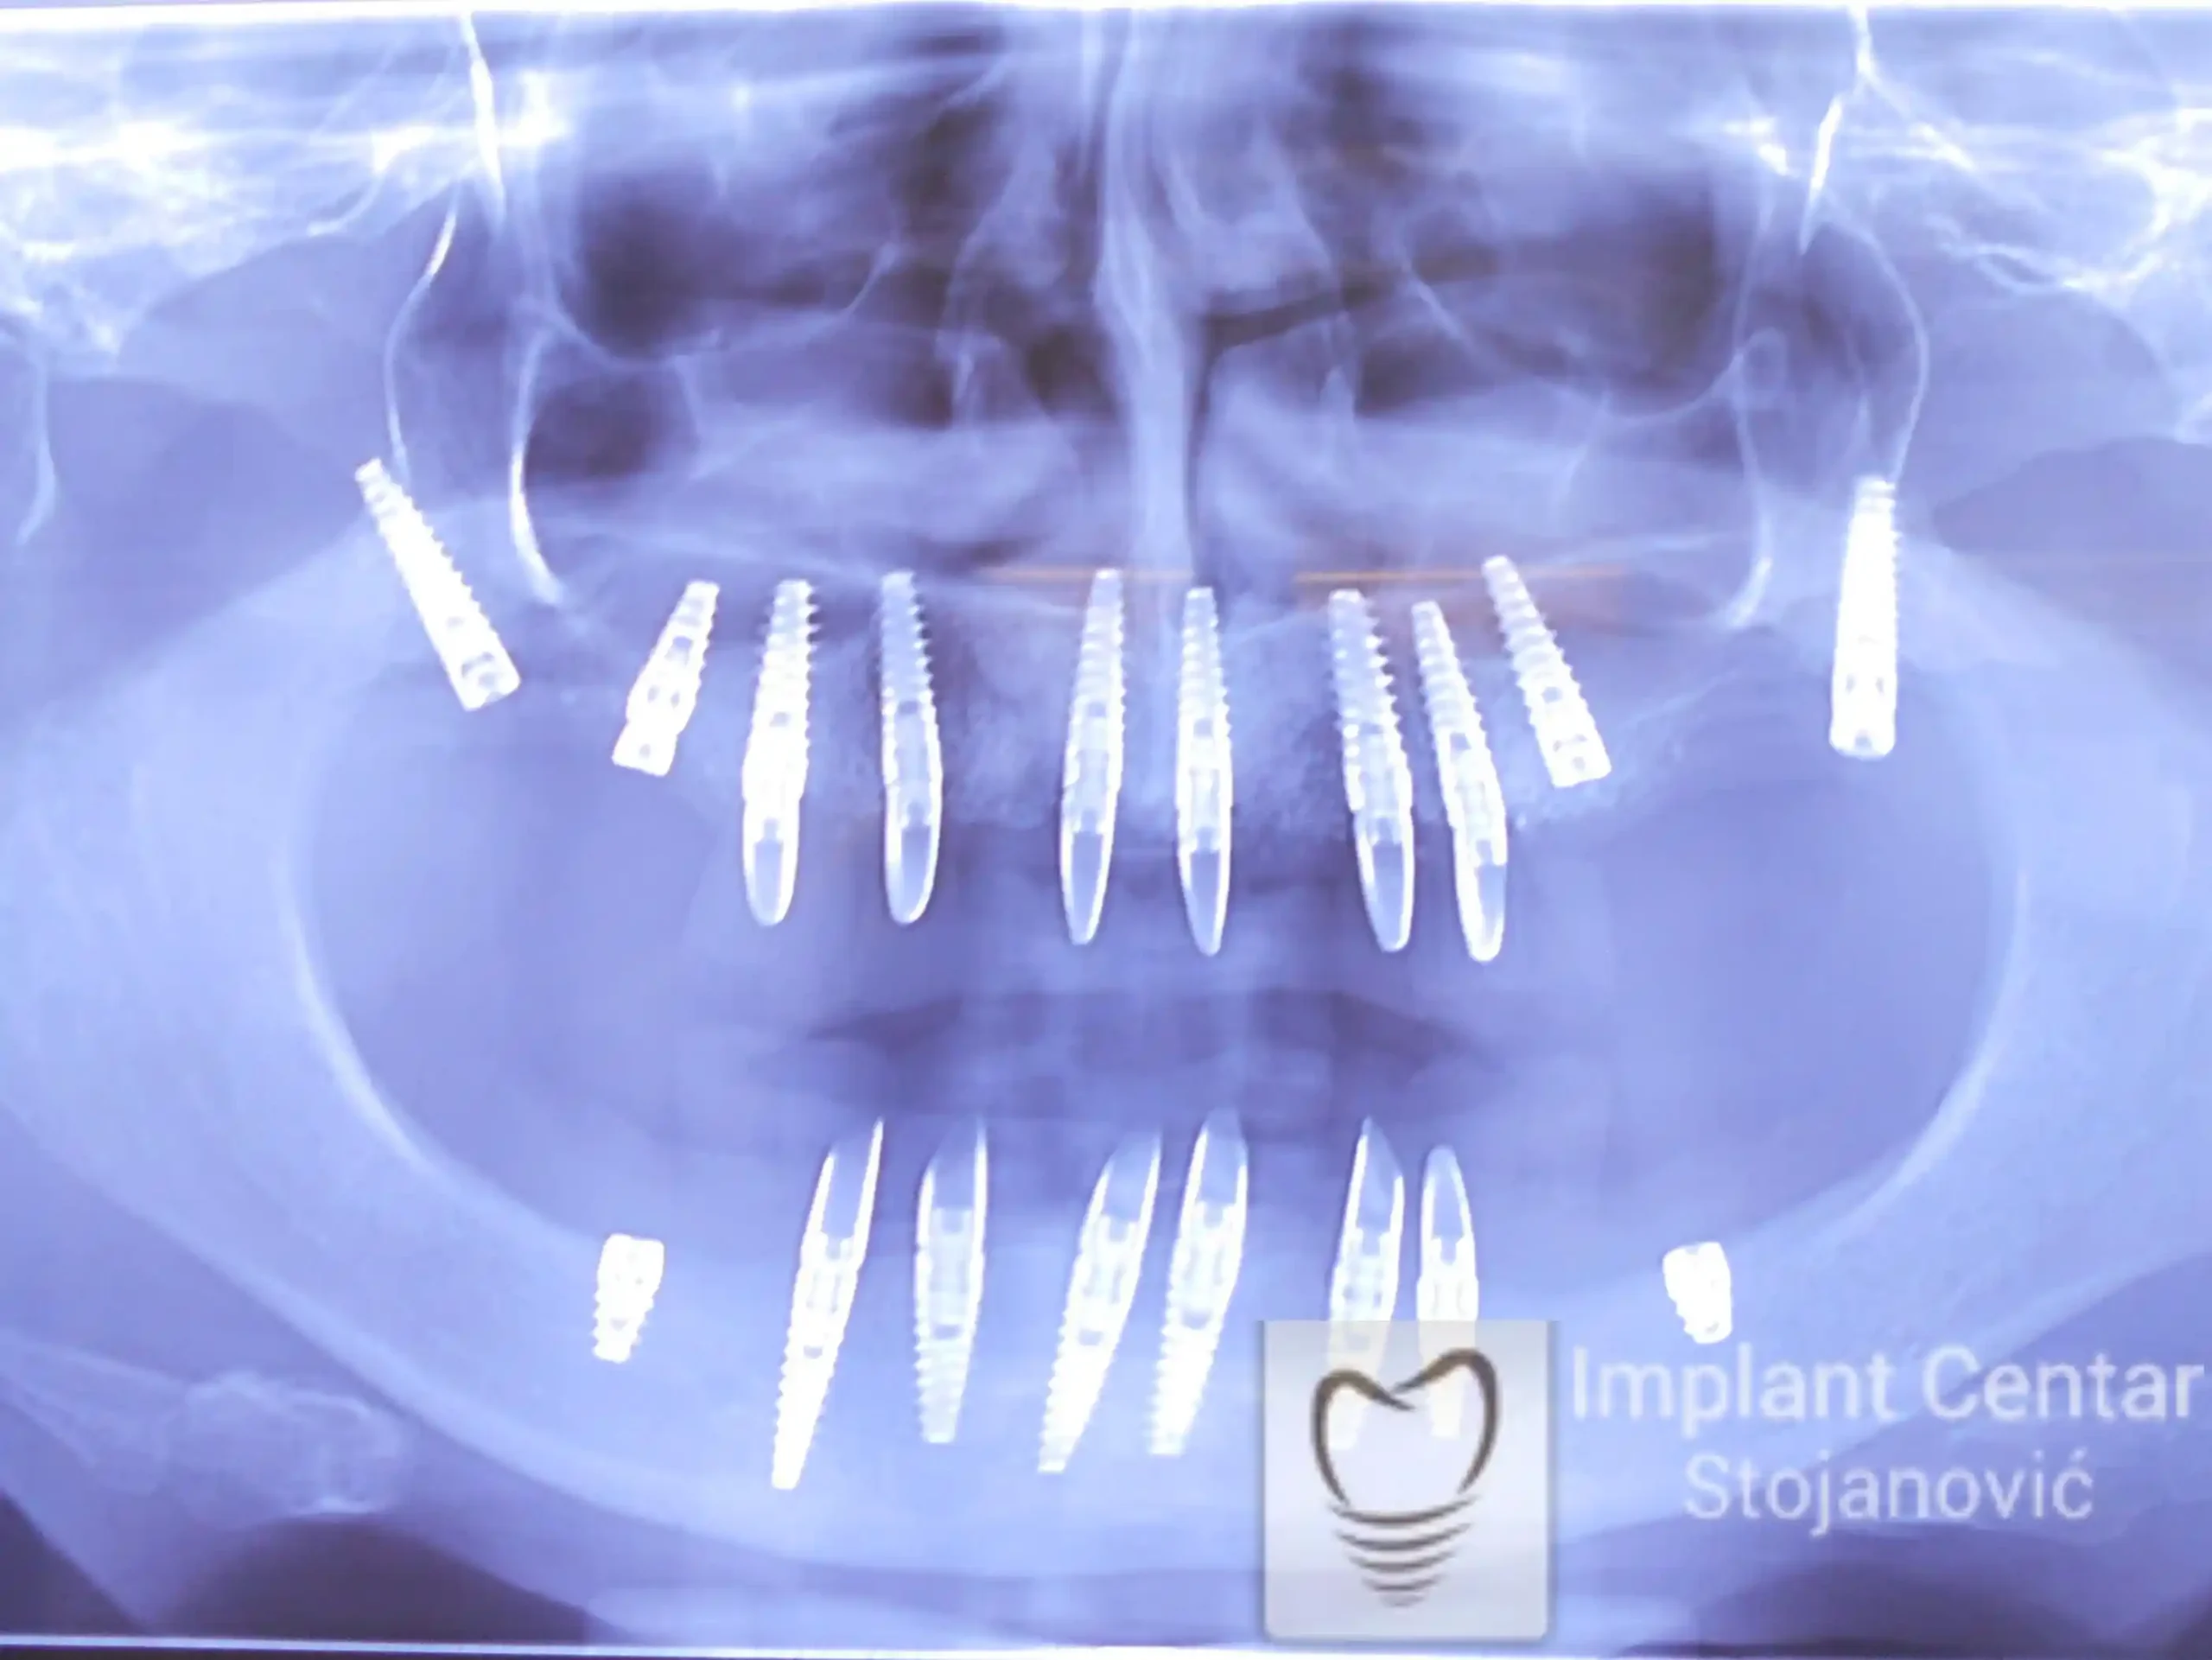

Nakon vađenja zuba, ugrađeni su implantati. Na slici 3 prikazan je ortopan snimak sa ugrđenim implantatima. Tokom perioda osteointegracije, pacijent je bio zbrinut fiksnim privremenim krunicama na implantatima, koje su izrađene samo dva dana nakon hirurške intervencije.

Zbog toga je plan terapije uključivao vađenje svih preostalih zuba i ugradnju implantata u gornjoj i donjoj vilici. U gornjoj vilici postavljena su i dva tuberopterigoidna implantata, kao zamena za sinus lift proceduru, što se može videti na ortopan snimku nurađenom odmah nakon ugradnje (slika 3).